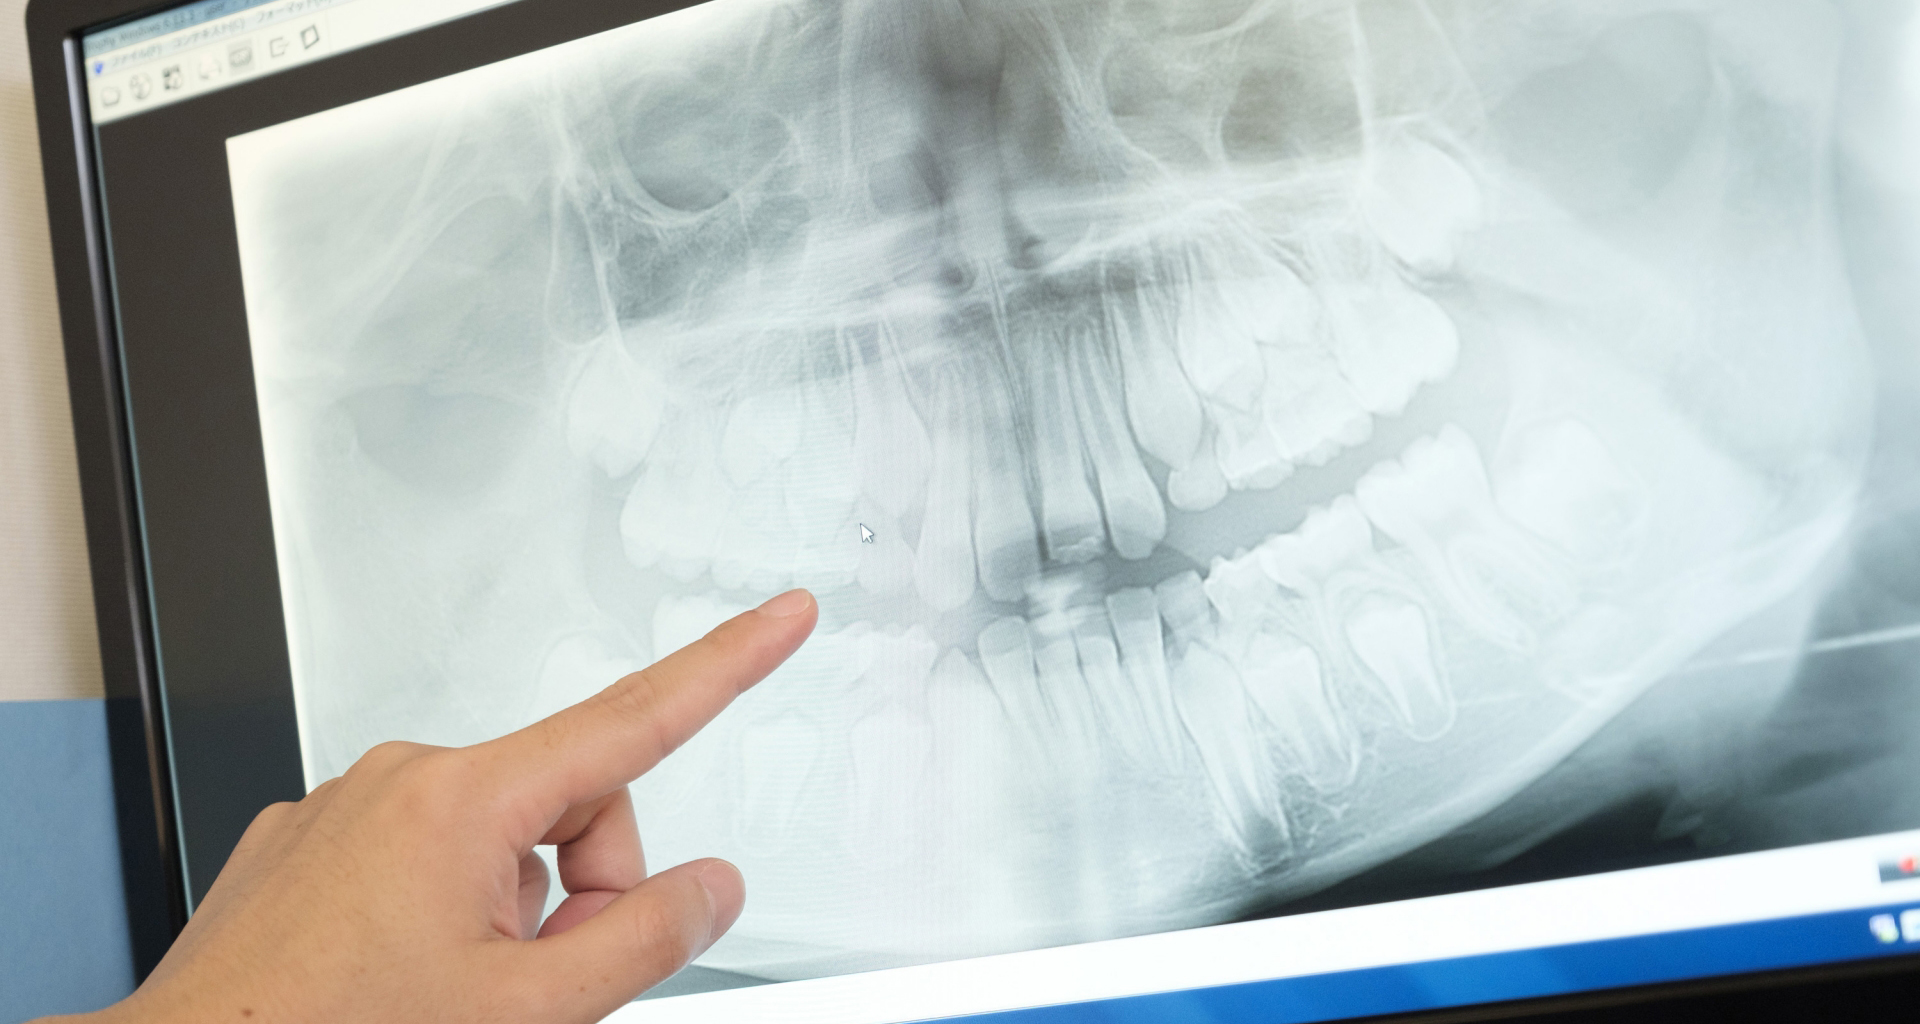

インレー症例

初診時パノラマ

初診時口腔内写真

iTero NIRI機能による診査

虫歯除去後

初診時バイトウィングデンタル

レントゲンだとちょっと虫歯が怪しいくらいに写っている。これだけだと確定診断としては、判断材料が少ないと考えられる。

黄色丸の部位が、他の部位と違って白く抜けがあるのがわかります。これがNIRI機能による虫歯の診査です。

この機能のおかげで、歯と歯の間の見つけにくい虫歯がよくわかるようになってきました。

In(インレー)セット後

当院では自費のインレー(つめ物)の場合、ゴムのシートをかけてから詰めていきます。

ゴムのシートをすることで、歯面を最大限乾燥することができ、接着力が上がる他、操作時の材料の誤飲の防止、接着剤の歯肉縁下(歯ぐきの中)への侵入を防止するなどといったメリットがあります。(歯の並びによっては、ゴムのシートができないことがあります。また、シートをかけることで苦しくなる、苦手という方には無理に行いません。)

年齢・性別 40代・男性

主訴 左上の奥歯がしみることがある

治療内容 左上4の虫歯

治療期間 2週間

リスク・副作用 虫歯の大きさによっては、神経をとらないといけなくなることがあります。

また、虫歯が大きかったケースで神経を残した場合、治療後にしみるなどの

症状が続くことがあります。

費用 ・ジルコニアインレーで修復

55,000円

治療方針

IOSのNIRI機能によって虫歯部分が明らかになったので、虫歯を除去後に修復治療を行うこととしました。

特記事項

ラバーダムは歯とつめ物をくっつける際に非常に効果的です。

人間は呼吸をしますので、お口の中はかなり湿度が高くなっています。水が多い状態でものをくっつけようと思ってもなかなかくっつかないということと同じになります。

ですので、呼気中の湿度に左右されないようにするために、ラバーダムを用いて接着力を高くしています。

ラバーダムで息が苦しくなる場合は使用しませんし、ラバーのアレルギーがある場合も使用できません。

担当医師所見

虫歯の有無を確認する上で今まではレントゲンと自分の目での確認でした。現在は目で見るよりもはるかにわかりやすいIOSという装置がありますので、虫歯の発見がしやすくなりました。

そのため、患者さんの虫歯の進行の段階が早いうちにわかる様になり、神経をとらなければならないというケースが非常に少なくなっています。